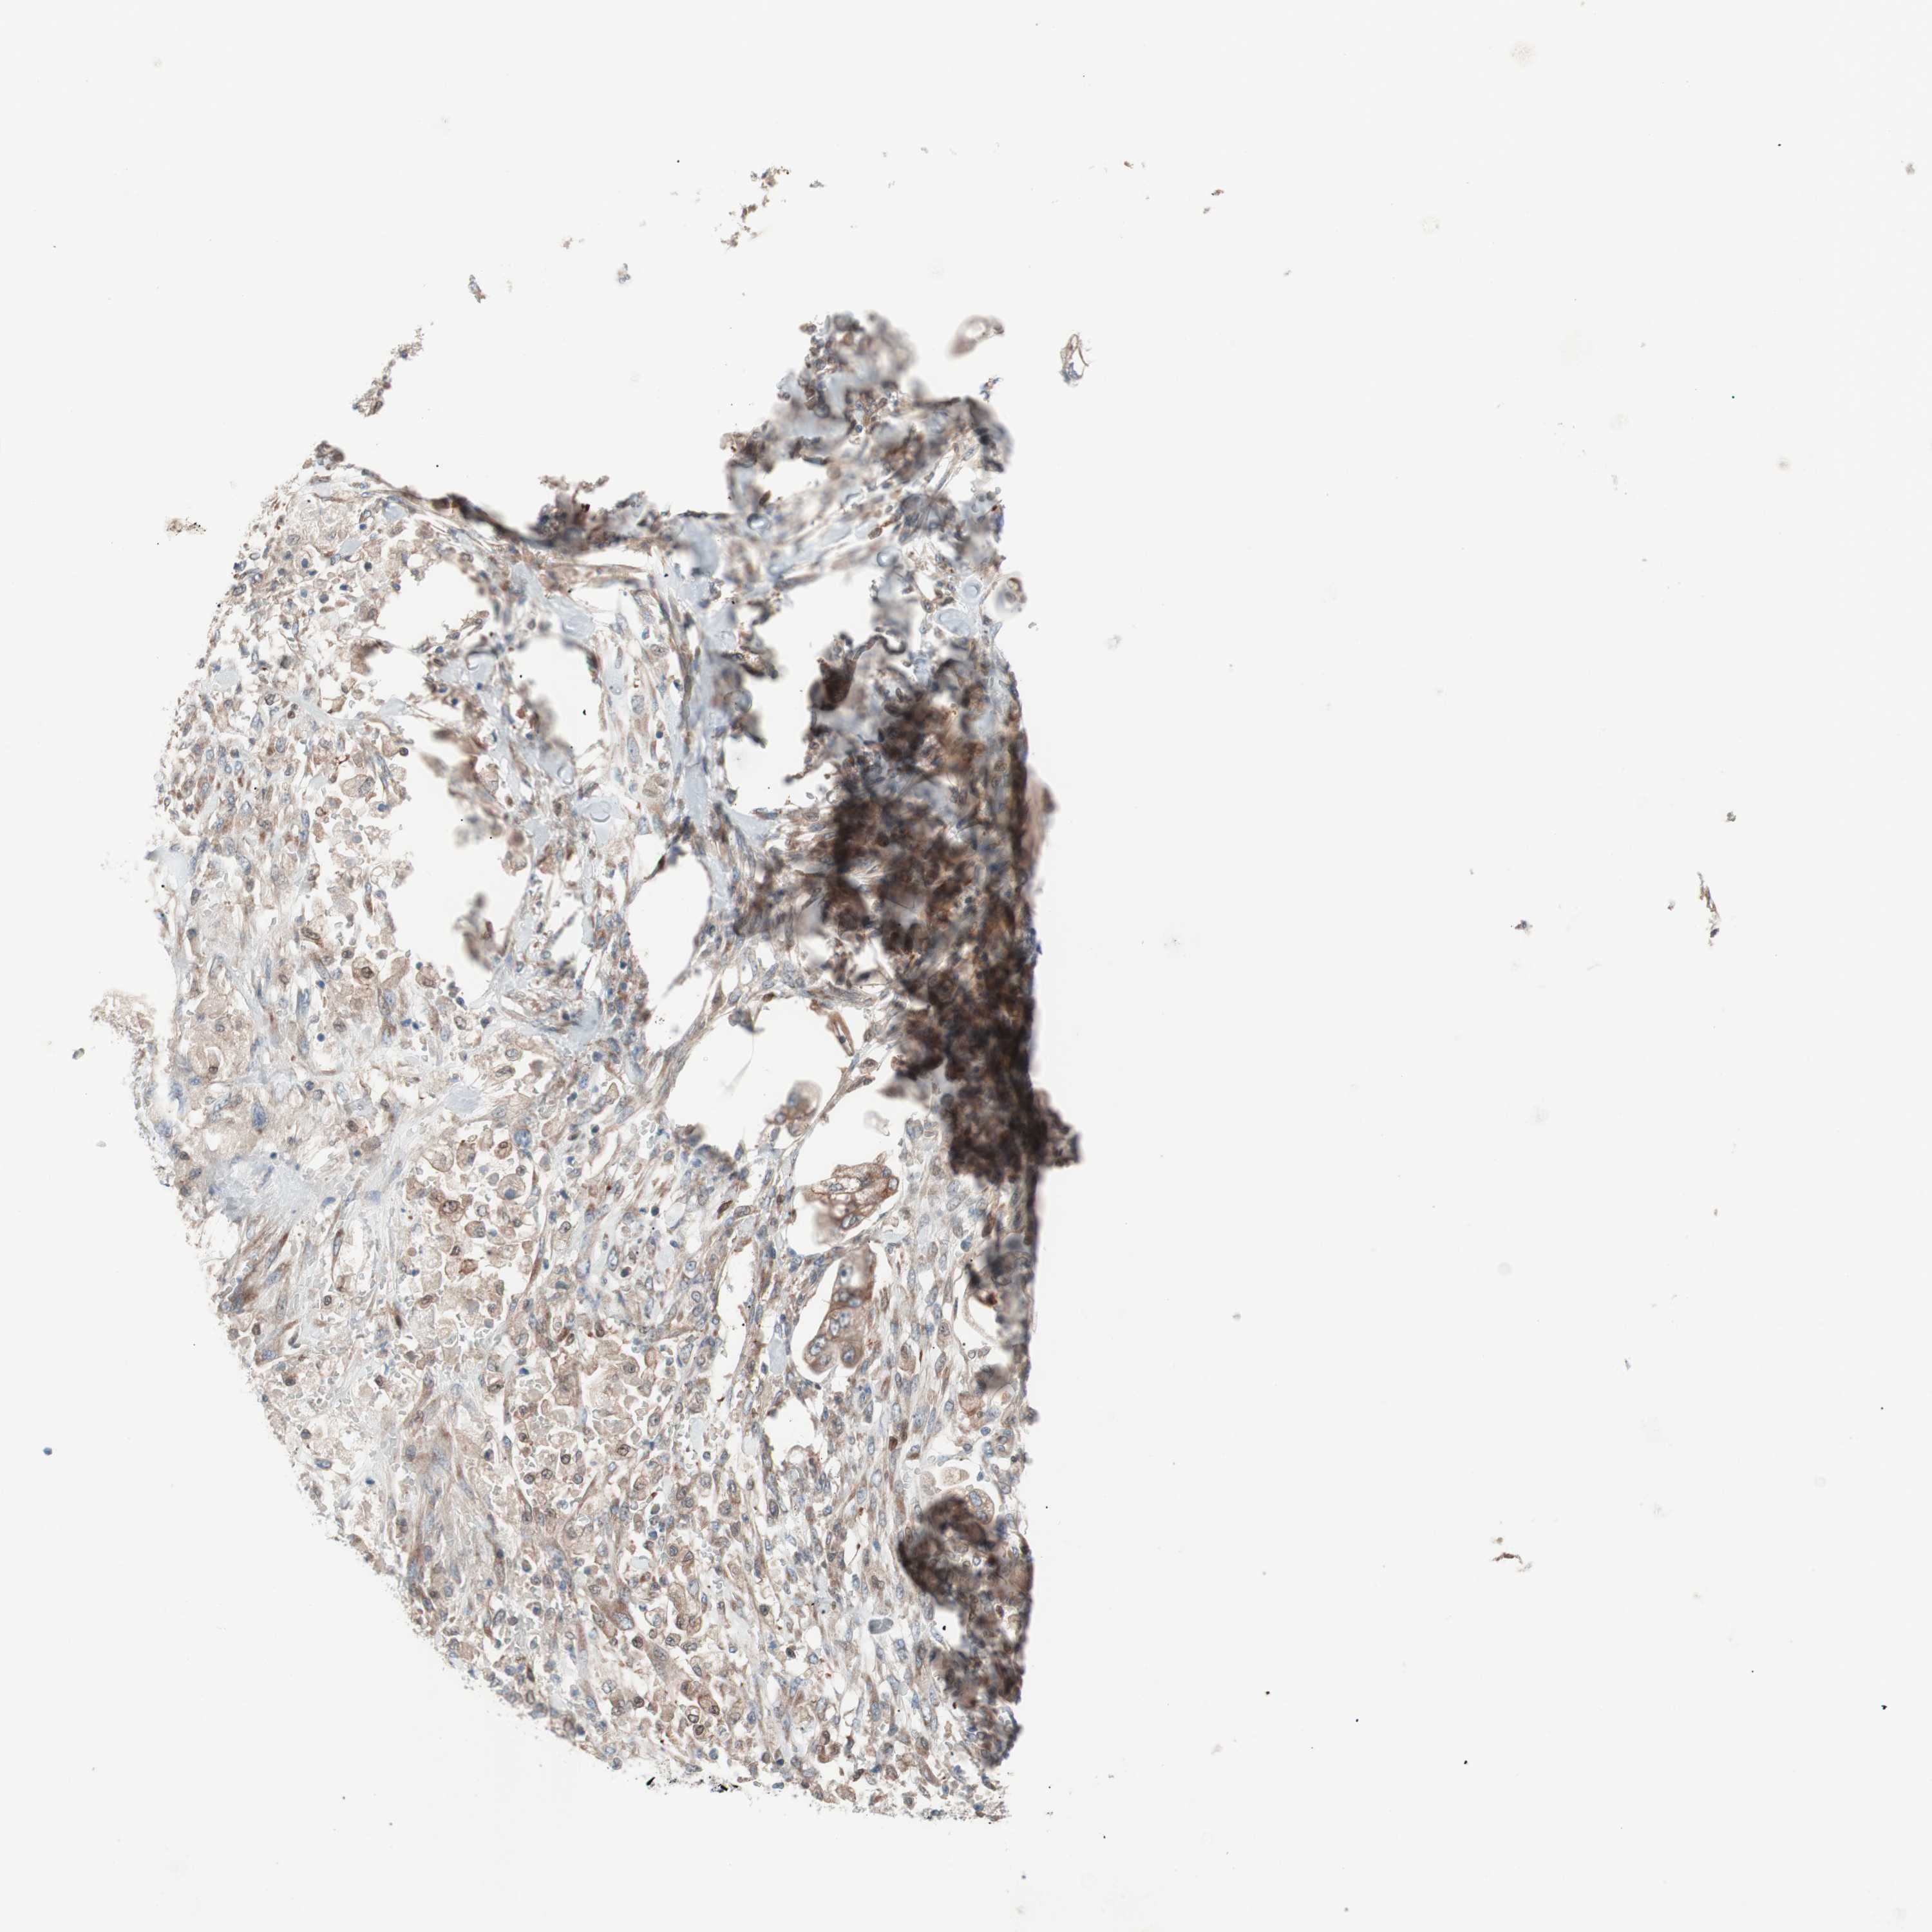

STOMACH CANCER - Protein expressioni

A mouse-over function shows sample information and annotation data. Click on an image to view it in a full screen mode. Samples can be filtered based on level of antibody staining by selecting one or several of the following categories: high, medium, low and not detected. The assay and annotation is described here.

Note that samples used for immunohistochemistry by the Human Protein Atlas do not correspond to samples in the TCGA dataset.

Antibody stainingi

Antibody staining in the annotated cell types in the current human tissue is reported as not detected, low, medium, or high, based on conventional immunohistochemistry profiling in selected tissues. This score is based on the combination of the staining intensity and fraction of stained cells.

Each image is clickable and will lead to virtual microscopy that enables deeper exploration of all samples and also displays staining intensity scores, fraction scores and subcellular localization as well as patient and tissue information for each sample.

Antibody HPA007425

Staining

High

Medium

Low

Not detected

Intensity

Strong

Moderate

Weak

Negative

Quantity

>75%

75%-25%

<25%

None

Location

Nuclear

Cytoplasmic/membranous

Cytoplasmic/membranous,nuclear

Adenocarcinoma, NOS

Adenocarcinoma, High grade